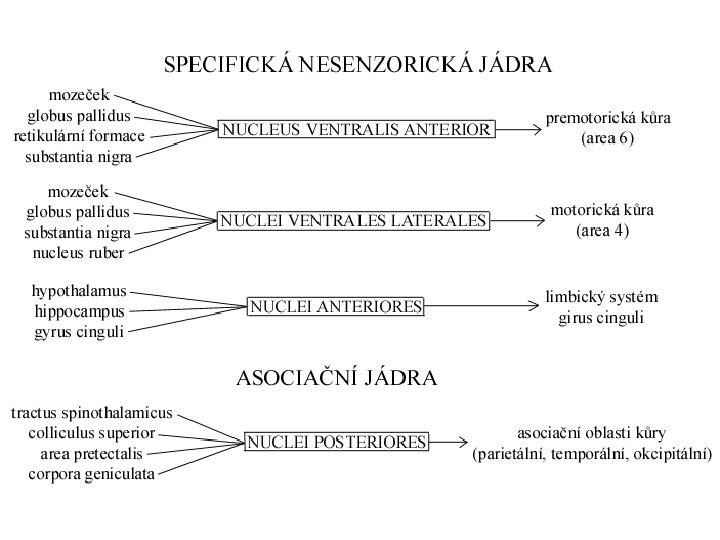

Thalamus (thalamus dorsalis) • • • „sekretářka mozku“ vše kromě čichu pulvinar (dorzálně) tuberculum anterius (ventrálně) lamina medullaris medialis + lateralis thalami adhesio interthalamica (80 %) – bez významu jádra se rozdělují se podle polohy nebo zapojení – nuclei anteriores, dorsales, intralaminares, mediani, mediales, posteriores, ventrales, reticularis – specifická senzorická jádra – specifická nesenzorická jádra – nespecifická jádra – asociační jádra

Třídění thalamických jader dle polohy nuclei anteriores, dorsales, intralaminares, mediani, mediales, posteriores, ventrales, reticularis

Specifická jádra • tractus mamillothalamicus ncl. anterior gyrus cinguli – opakované kroužení zesiluje emoce • globus pallidus ncl. VA prefrontální kůra • globus pallidus ncl. VL doplňková motorická kůra • nucleus dentatus cerebelli ncl. VL motorická kůra • lemniscus medialis et spinalis ncl. VPL senzitivní kůra • lemniscus trigeminalis ncl. VPM senzitivní kůra

Asociační jádra • ncl. LD (lat. dors. ) area cingularis posterior • čichový a limbický mozek ncl. MD (mediodors. ) prefrontální kůra (myšlení, úsudek, nálada, stav mysli – integrace se smyslovými podněty) • colliculus superior ncl. LP (lat. post. ) + pulvinar zraková a parietální asociační kůra (přitahuje pozornost k objektům v periferii zrakového pole) • ncll. P (pulvinar) frontální, temporální, parietální a okcipitální asociační kůra (integrace zrakových, sluchových, hmatových a polohových podnětů)

Nespecifická jádra • ncll. intralaminares – pomalá bolest – ARAS • ncll. mediani • limbický systém (dle eferentace)